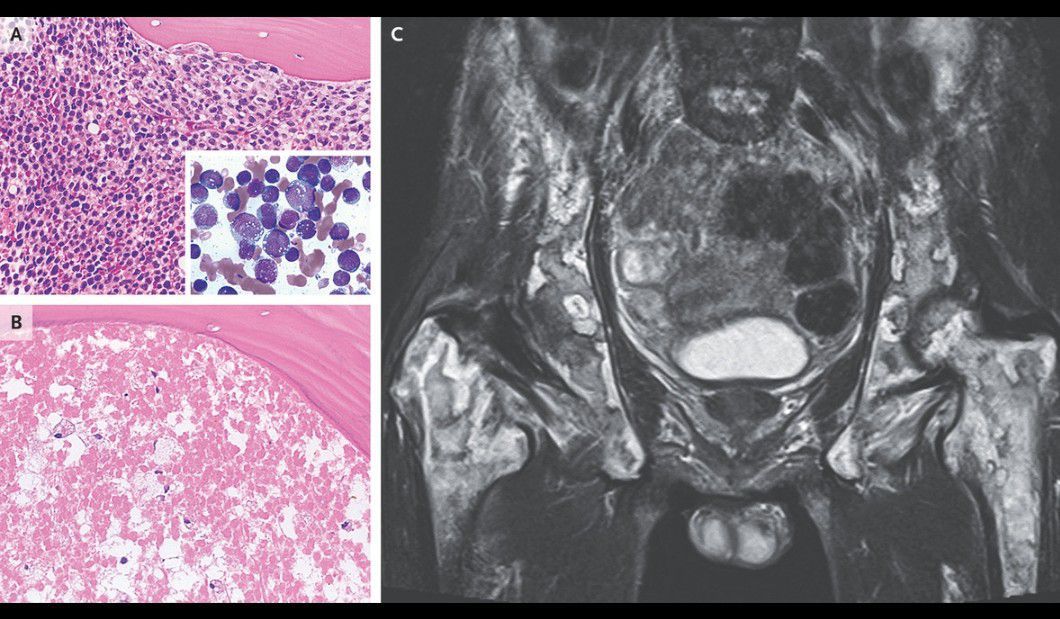

A 56-year-old man presented to an outpatient clinic with a 7-day history of fever, mild fatigue, and shortness of breath. On physical examination, his abdomen was nontender and distended, with hepatomegaly and splenomegaly, and cervical lymphadenopathy was noted. Laboratory studies revealed a white-cell count of 142,000 per microliter (reference range, 3500 to 9800) with 92% monoblasts, a hemoglobin level of 7.6 g per deciliter (reference range, 13.5 to 17.5), and a platelet count of 36,000 per microliter (reference range, 130,000 to 370,000). A bone marrow biopsy revealed leukemic infiltration of the marrow with monoblasts (Panel A, bone marrow specimen stained with hematoxylin and eosin; inset, aspirate smear stained with May–Grünwald–Giemsa). A diagnosis of acute monoblastic leukemia was made, and the patient received induction chemotherapy. Diffuse alveolar hemorrhage and acute kidney injury subsequently developed in the context of disseminated intravascular coagulation and tumor lysis syndrome. After the patient’s condition improved, he began having persistent lower back pain. Pelvic bone marrow specimens showed diffuse ghost cells indicative of necrosis (Panel B). Magnetic resonance imaging of the pelvis revealed areas of high and low signal intensity that had a marble-like appearance, findings that suggested necrosis of hematopoietic and stromal elements (Panel C). The patient underwent allogeneic stem-cell transplantation; however, the leukemia recurred and he died 4 months later.